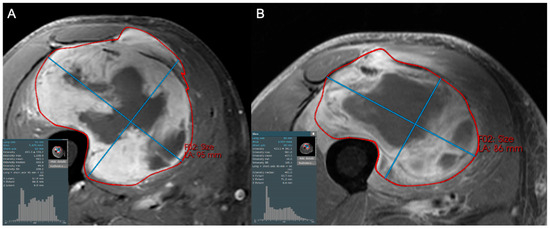

- Valenzuela, R.; Duran-Sierra, E.; Canjirathinkal, M.; Amini, B.; Torres, K.; Benjamin, R.; Ma, J.; Wang, W.; Hwang, K.; Stafford, R.; et al. Radiomics by Quantitative Diffusion-weighted MRI for Predicting Response in Patients with Extremity Soft-tissue Undifferentiated Pleomorphic Sarcoma. J. Radiol. Oncol. 2024, 8, 064–071. [Google Scholar] [CrossRef]